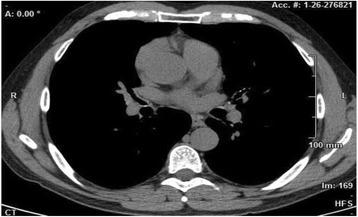

We report a case of a 49 year old male, non-smoker. He was a smith, homeless, born in Romania and reported a diagnosis of asthma since childhood. He was admitted to our Respiratory Unit presenting low-grade fever with profuse sweating, cough, purulent sputum, and ground-glass opacity with irregularity in main bronchi detected by High-Resolution Computed Tomography (HRCT) scan. Fibrobronchoscopy revealed the presence of mucosal irregularities up to the segmental bronchi entrance. Histological examination showed nodules of osseouscartilaginous nature, consistent with TBPO. Microbiological tests of Bronchoalveolar Lavage fluid also revealed an infection by Pseudomonas Aeruginosa.

我们报告一例49岁男性,非吸烟者。他是一名铁匠,无家可归,出生于罗马尼亚,自幼被诊断为哮喘。他因低热、多汗、咳嗽、脓性痰入院,高分辨率计算机断层扫描(HRCT)显示主支气管有磨玻璃样混浊及不规则影。纤维支气管镜检查显示直至段支气管入口处均有黏膜不规则。组织学检查显示为骨软骨性质的结节,符合TBPO。支气管肺泡灌洗液体的微生物学检测还显示有铜绿假单胞菌感染。